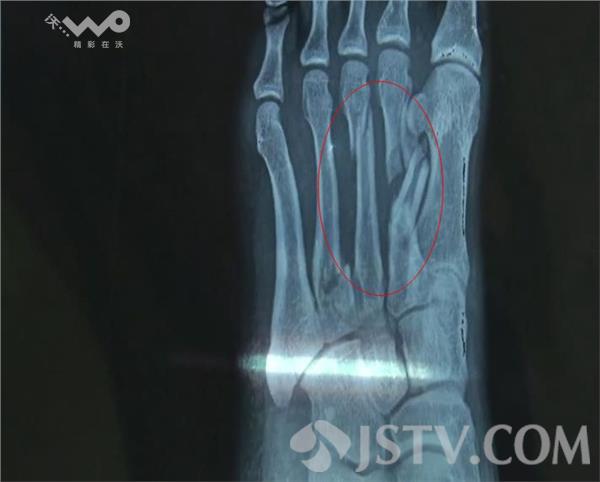

在灌云县人民医院的八楼病房里,张长余躺在病床上,左脚肿胀得像个馒头,通过医院拍摄的X光片可以看到,左脚有四根骨头断裂,其中还有两根已经错位。张长余告诉记者,事情发生在1月2日的下午3、4点钟左右,他驾驶摩托车经过灌河大桥时,发现桥上围了不少人,在得知有人轻生跳河的情况后,就赶忙沿桥边的人行道向南跑,到南岸的水泥驳堤边后就跳了下去,然后沿着河边一路向东,最终在距离大桥约三百米左右的地方,将轻生的女子拉了上来,直到这个时候,他自己才发现脚受伤了,此时疼得已经无法再走路。